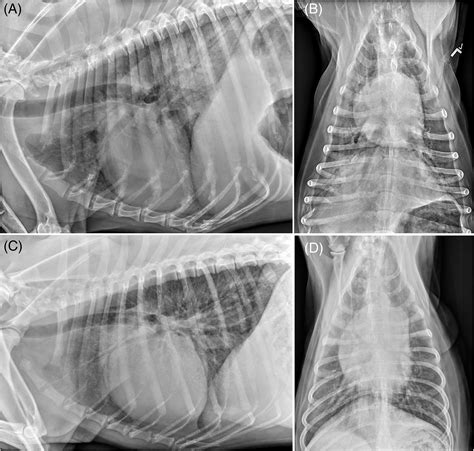

Chest X-rays

Chest X-rays provide a detailed image of the lungs and surrounding structures. They can help identify abnormalities such as inflammation, fluid accumulation, or tumors. X-rays are a non-invasive and relatively quick procedure, making them a valuable tool in diagnosing canine lung disease.